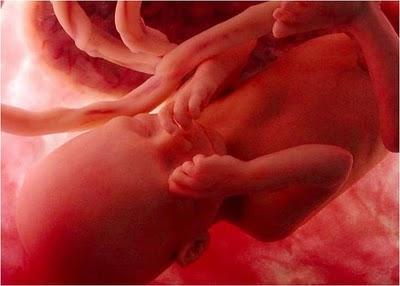

Las imágenes utilizadas en esta presentación son parte del documental "En el vientre materno" producido por National Geographic.

Son imágenes obtenidas a través de una micro-cámara introducida en el útero de una gestante. Gracias a las modernas técnicas fotográficas es posible acompañar el fascinante proceso de gestación de un bebé.

UN EMBRIÓN DE POCAS SEMANAS QUE SE ENCUENTRA EN EL INTERIOR DEL ÚTERO DE SU MADRE.

ESTÁ EN EL INICIO DE SU DESARROLLO.

ES APENAS EL PRINCIPIO DE UN SER HUMANO Y EN ESTE ESTADO PODRÍA SER CONFUNDIDO CON EL EMBRIÓN DE UN MACACO.

JUNTO A ÉL SE ENCUENTRA EL SACO VITELINO,PROPORCIONÁNDOLE LOS NUTRIENTES QUE NECESITAEN LAS PRIMERAS SEMANAS DE VIDA.

ALREDEDOR DE LA 8ª SEMANA DE GESTACIÓN EL SACO VITELINO PIERDE SUS FUNCIONES. EL CORDÓN UMBILICAL EMPEZARÁ AALIMENTARLO CON NUTRIENTES TOMADOS DELCUERPO MATERNO A TRAVÉS DE LA PLACENTA.

MIENTRAS TODO ESTO SUCEDE, ÉL FLOTA TRANQUILAMENTE,EN EL ÚTERO DE SU MADRE.